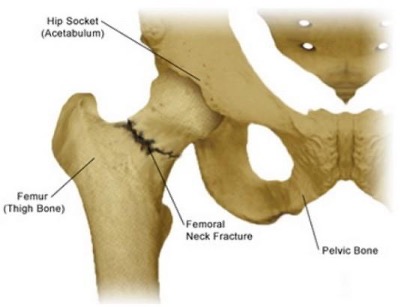

- Femoral Neck Fracture – Femoral neck fractures, which tend to affect older adults and can be linked to osteoporosis. They happen in the bone just below the ball – of the ball in the socket. These may be fixed if simple and stable, but often require replacement.

- Not Displaced Femoral Neck – In-situ pinning is the standard treatment option for a femoral neck fracture that has yet to become displaced. During this surgery, screws or pins are placed across the injury site to secure the ball of the femur as it heals. Newer treatments with plutes may be deemed more appropriate.

- Displaced Femoral Neck – Elderly patients suffering from displaced fractures of the femoral neck are typically advised to undergo a hemiarthroplasty or partial hip replacement; however, certain individuals may experience greater functionality with total hip replacement despite an increased risk of complications. Total hip replacement is also highly recommended for younger and more active patients.